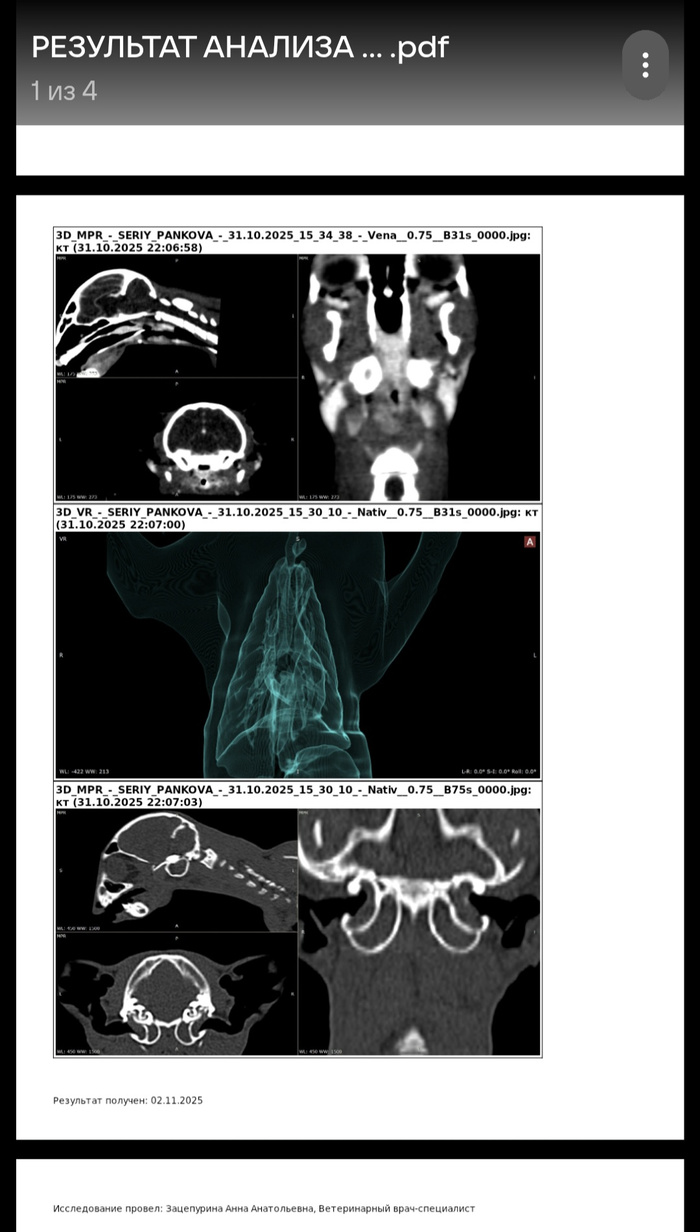

Пришло заключение, уже вчера ближе к ночи.

Ожидалось что-то другое, может связанное с циторогией и бакпосевом. А тут что-то непонятное на причьем языке. Похоже это что-то совсем нехорошее, в процесс втянуты обе барабанные камеры. Интересно, он хоть слышит?

Полночи гуглила, пыталась понять. Поняла только то, что и полипы и стеноз лечат только операцией.